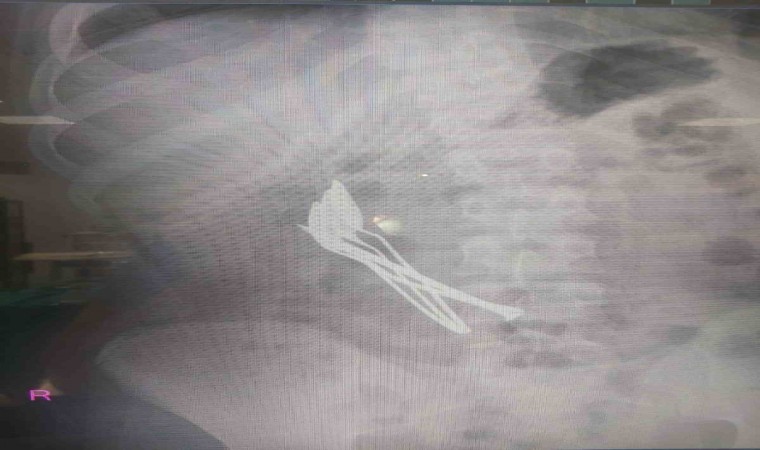

Kayseri’de mide ağrısı şikayetiyle hastaneye başvuran çocuğun midesinden 4 metal kaşık ve 1 çivi çıkarıldı.

Kentte yaşayan 15 yaşındaki çocuk, mide ağrısı şikayetiyle Kayseri Şehir Hastanesine başvurdu. Yapılan ilk müdahalede çocuğun röntgeni çekilirken, midesinde cisim fark edildi. Çocuk Cerrahisi ve Ürolojisi Anabilim Dalı Başkanı Doç. Dr. Mustafa Erman Dörterler tarafından ameliyata alınan çocuğun midesinden 4 adet metal çay kaşığı ve çivi çıkarıldı.